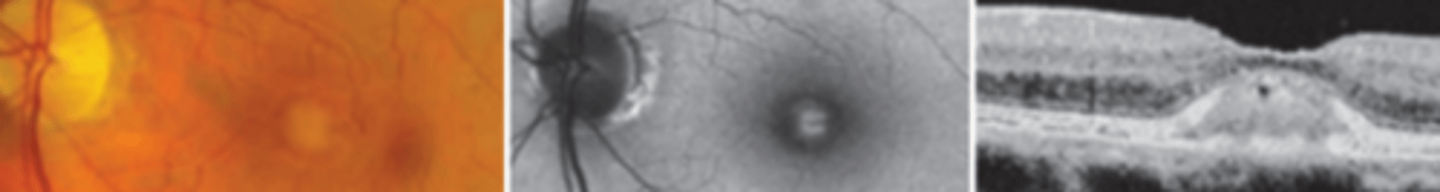

Best vitelliform macular dystrophy (BVMD)

an autosomal dominant disease resulting in mutation of the bestrophin gene. This results in bilateral subretinal ("egg yolk") deposits due to excessive lipofuscin accumulation in the RPE. Has a juvenile onset (3-15 yo). Patient will have abnormal EOG even when the fundus appears normal. ERG results will be normal. There is no treatment, however prognosis is good up until the 5th decade. Refer to low vision and for genetic testing.

1.5

Patients with best macular dystrophy will have Arden ratios below...

0

stage of best macular dystrophy where the fundus is normal, but EOG is abnormal

1 (pre-vitelliform)

stage of best macular dystrophy where there is pigment mottling at the macula

2 (vitelliform)

stage of best macular dystrophy where there are yellow egg yolk lesions at the macula (1st to 2nd decade)

3

stage of best macular dystrophy where there is a pseudo hypopyon

4 (vitelleruptive, atrophic)

stage of best macular dystrophy where there is RPE atrophy or CNVM due to break up of lipofuscin

Macular scarring, CNVM, geographic atrophy

legal blindness may occur in Best macular dystrophy is one of these three retinal events occur

Adult onset Foveomacular Vitelliform Macular Dystrophy (AOVMD)

an autosomal dominant disease presenting in the 4th-6th decade as macular lesions often centered by a pigmented spot and darkened border, possibly a milder form of best's disease. Is asymptomatic to mild often misdiagnosed as early AMD. There is no treatment, but prognosis is good unless a CNVM forms.

Milder presentation (EOG normal or slightly abnormal, smaller lesions), older age of onset

two factors differentiating adult onset foveomacular vitelliform macular dystrophy from Best macular dystrophy

Butterfly-shaped Macular Dystrophy

an autosomal dominant disease presenting in the 2nd-6th decade as bilateral star shaped yellow lesions of the macula. Prognosis is good, CNVM and atrophic maculopathy rarely occurs. ERG may be slightly subnormal. EOG often depressed.